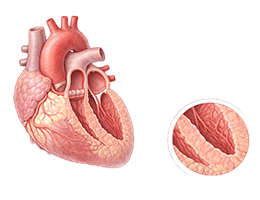

심근경색 (Myocardial Infarction)

협심증 (Angina Pectoris)

심근병증 (Cardiomyopathy)

심장판막질환 (Valvular Heart Disease)

심부전 (Heart Failure)

비대성심근병증 (Hypertrophic Cardiomyopathy)

확장성심근병증 (Dilated Cardiomyopathy)

울혈성심부전 (Congestive Heart Failure)

심근염 (Myocarditis)

심막염 (Pericarditis)

심내막염 (Endocarditis)

심정지 (Cardiac Arrest)

돌연심장사 (Sudden Cardiac Death)

심방세동 (Atrial Fibrillation)

심실빈맥 (Ventricular Tachycardia)

심실세동 (Ventricular Fibrillation)

서맥 (Bradycardia)

심장판막질환 (Heart Valve Disease)

폐동맥고혈압 (Pulmonary Hypertension)

심장병성쇼크 (Cardiogenic Shock)

심장막압전 (Cardiac Tamponade)

확장형심근병증 (Dilated cardiomyopathy)

비후성심근병증 (Hypertrophic cardiomyopathy)

제한성심근병증 (Restrictive cardiomyopathy)

감염성심내막염 (Infective endocarditis)